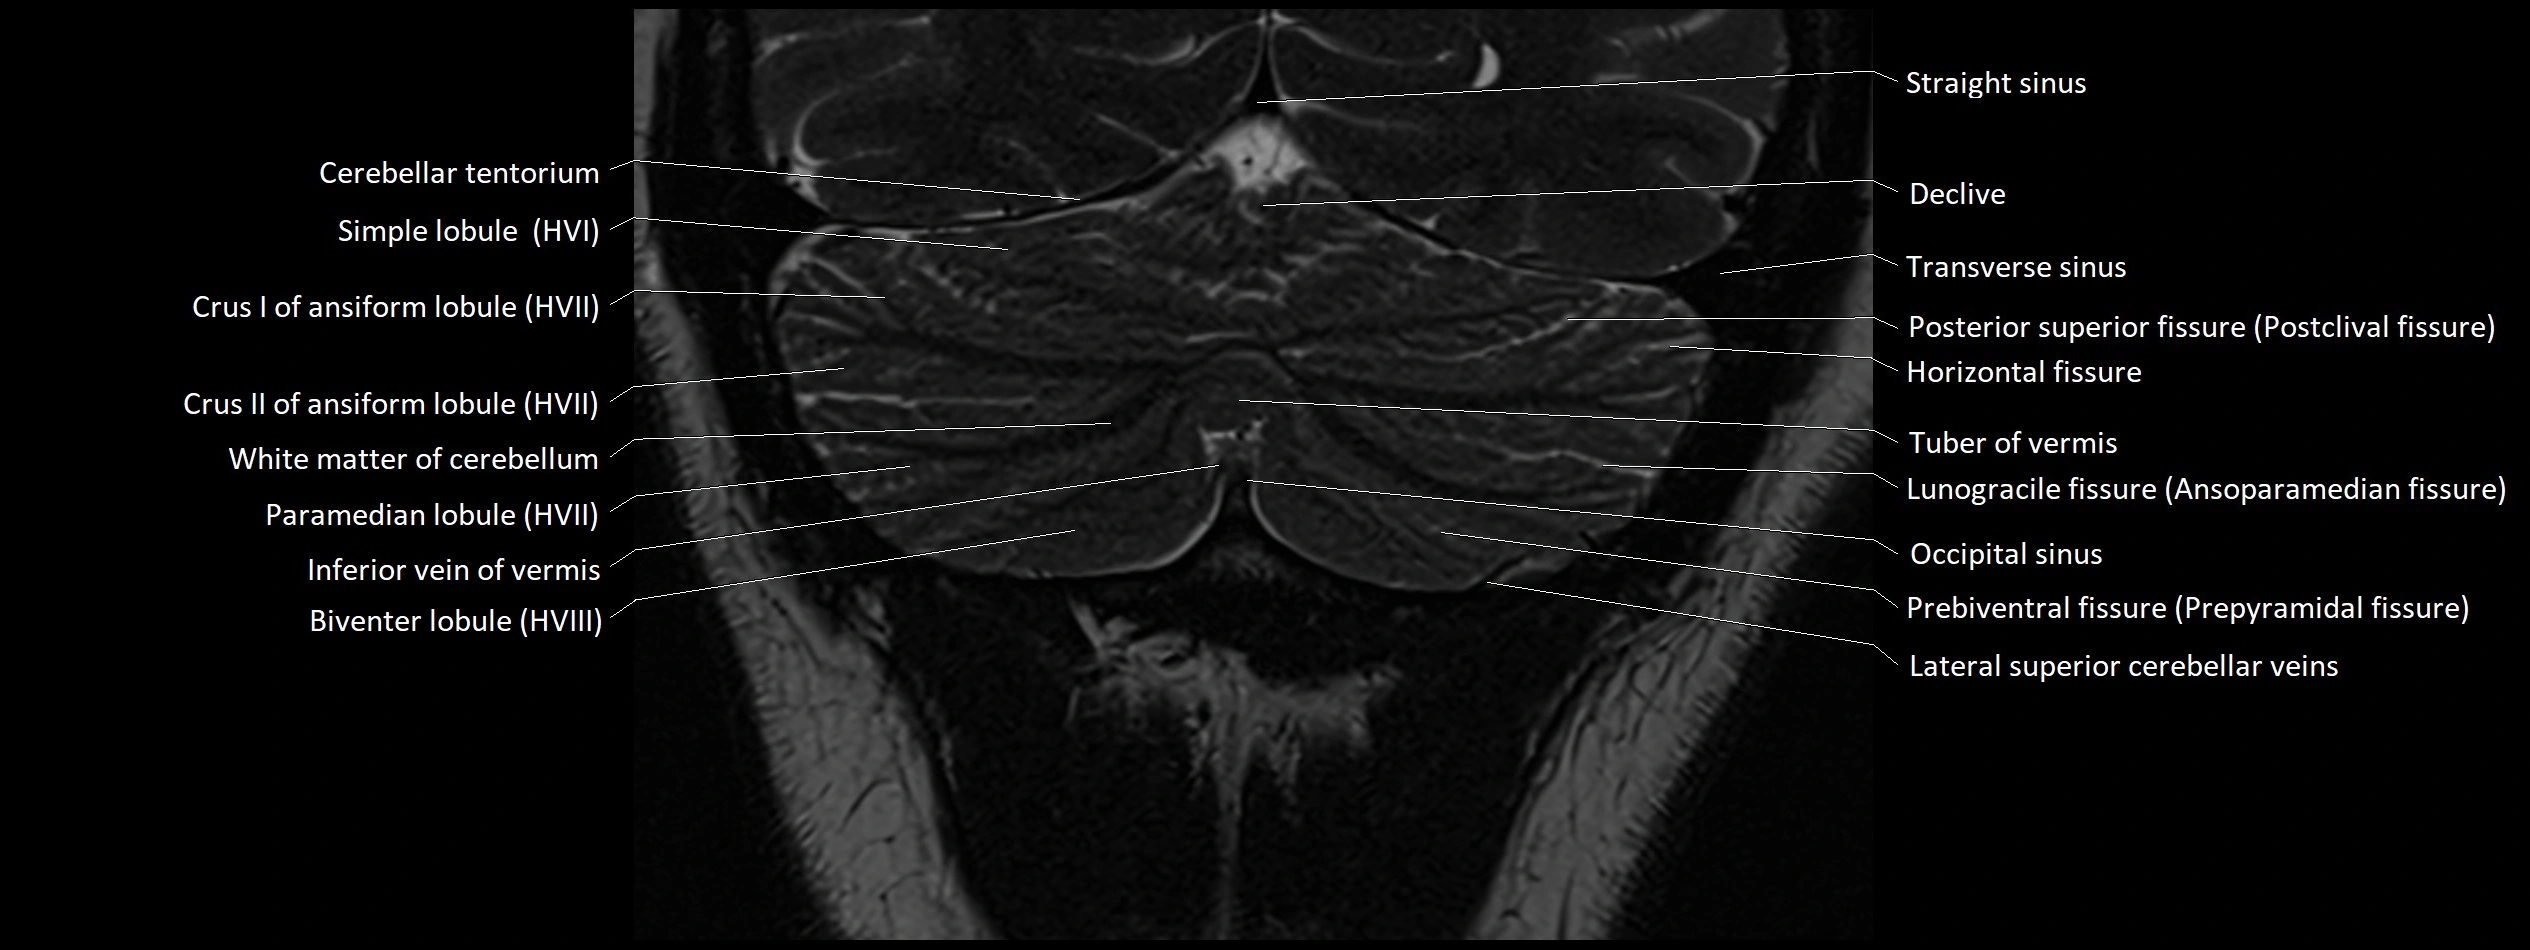

- Biventral lobule (HVIII) of cerebellum

- Cerebellar tentorium

- Crus II of ansiform lobule of cerebellum

- Declive

- Horizontal fissure (cerebellum)

- Inferior vein of vermis

- Lunogracle fissure

- Occipital sinus

- Paramedian lobule (HVII) of cerebellum

- Posterior superior fissure

- Prebiventral fissure

- Simple lobule (HVI) of cerebellum

- Straight sinus

- Transverse sinus

- Tuber of vermis

- White matter of cerebellum (Arbor vitae)